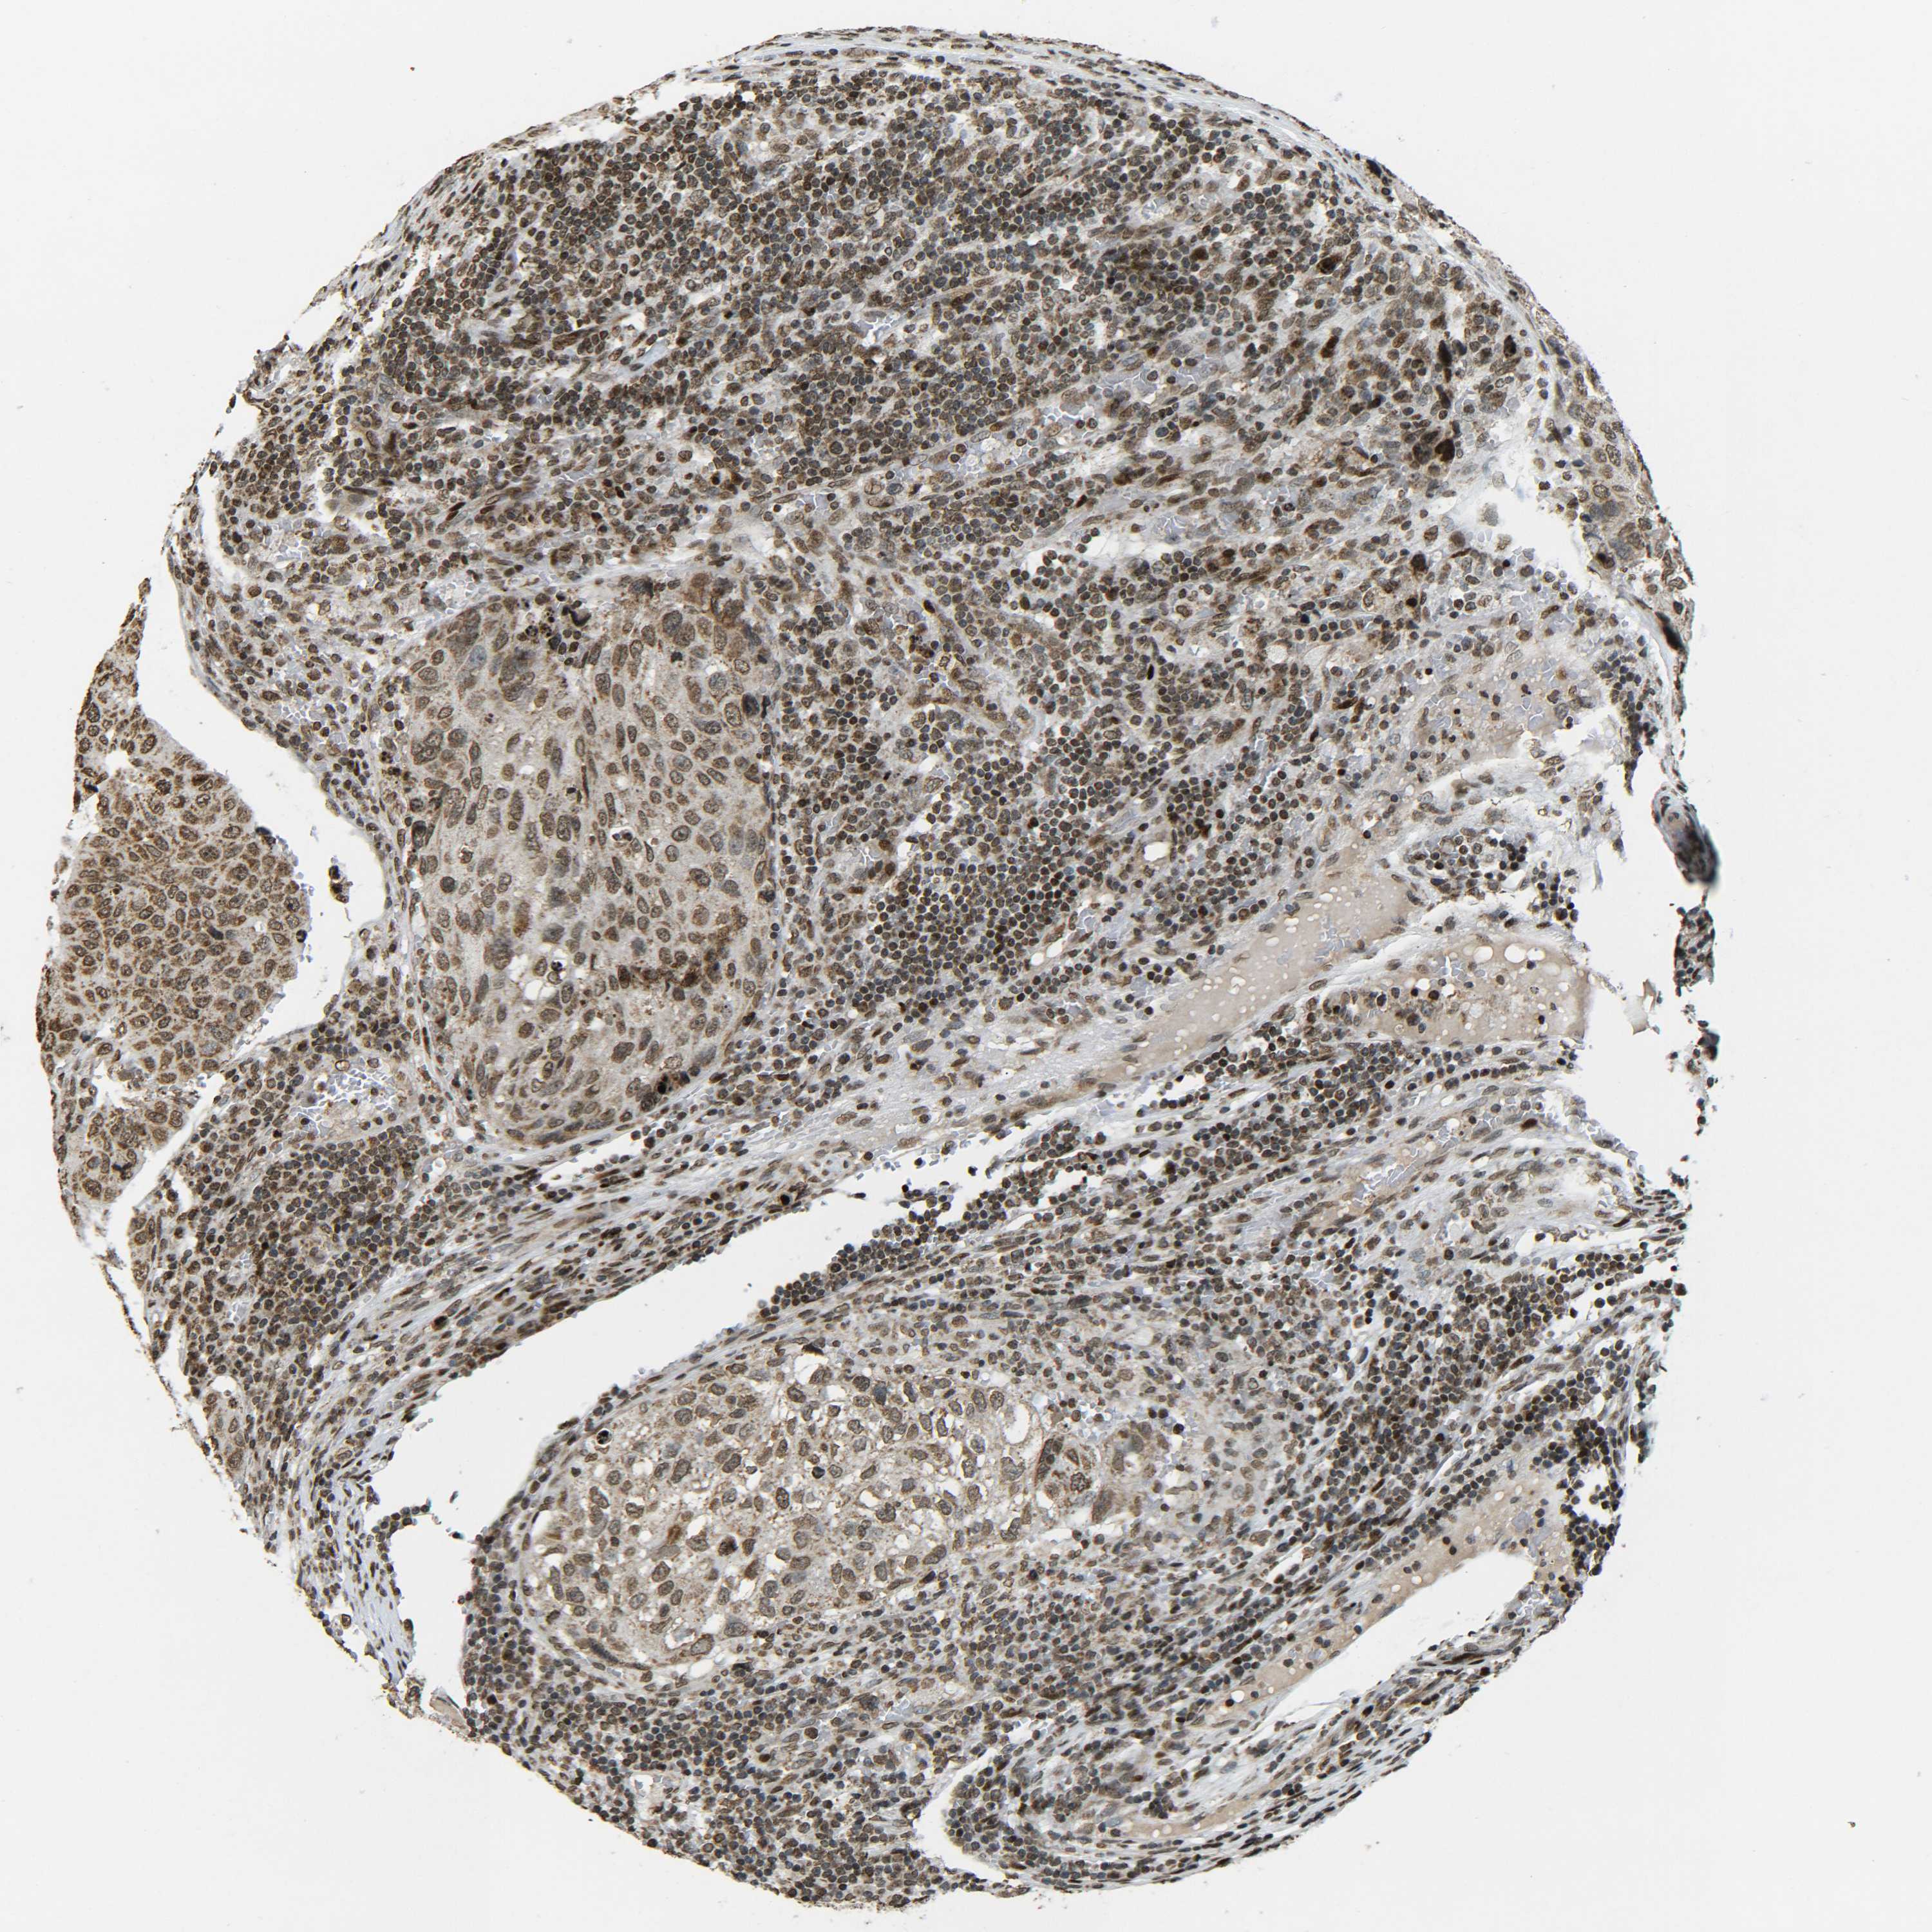

UROTHELIAL CANCER - Protein expressioni

A mouse-over function shows sample information and annotation data. Click on an image to view it in a full screen mode. Samples can be filtered based on level of antibody staining by selecting one or several of the following categories: high, medium, low and not detected. The assay and annotation is described here.

Note that samples used for immunohistochemistry by the Human Protein Atlas do not correspond to samples in the TCGA dataset.

Antibody stainingi

Antibody staining in the annotated cell types in the current human tissue is reported as not detected, low, medium, or high, based on conventional immunohistochemistry profiling in selected tissues. This score is based on the combination of the staining intensity and fraction of stained cells.

Each image is clickable and will lead to virtual microscopy that enables deeper exploration of all samples and also displays staining intensity scores, fraction scores and subcellular localization as well as patient and tissue information for each sample.

Antibody CAB012342

Staining

High

Medium

Low

Not detected

Intensity

Strong

Moderate

Weak

Negative

Quantity

>75%

75%-25%

<25%

None

Location

Nuclear

Cytoplasmic/membranous

Cytoplasmic/membranous,nuclear

Urothelial carcinoma, Low grade